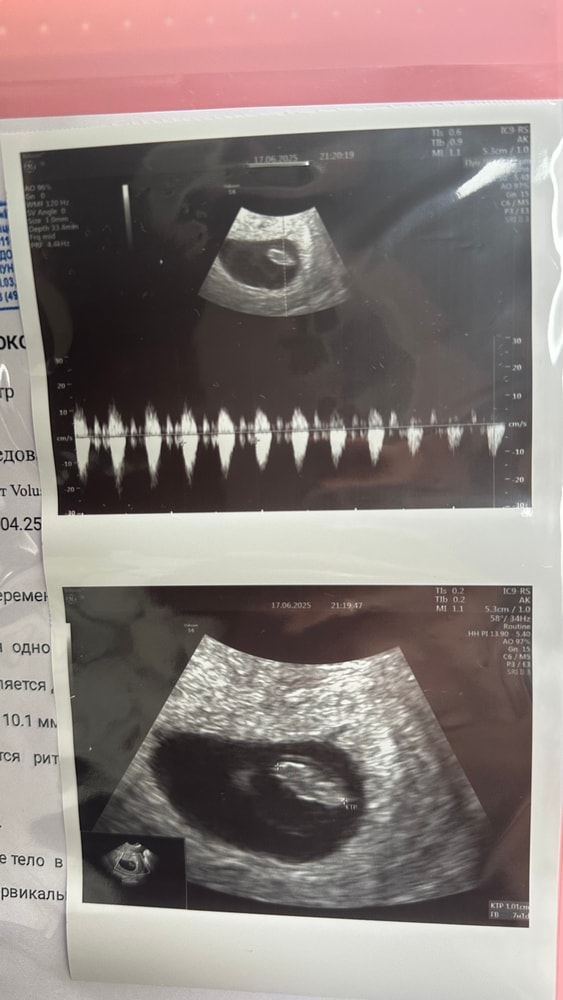

Мама мальчика (2 года), жду мальчика, 12 неделя

Всем привет! Сегодня бусинке 8 недель и 1 день, и мы передаем вам всем огромный привет и хотим зачихать вас всех самыми беременными чихами🤞🏽✨🤰🏻❤️